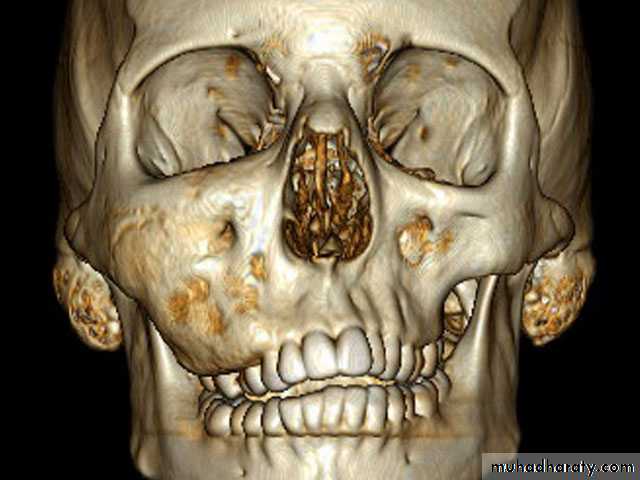

2- Fibrous dysplasia-Affect children- Replacement of normal bone by immature bone with extensive vascular fibrouselements.- Maxilla is more affected- painless enlargement of the maxilla on the affected side , buccal and palatalaspect of the bone may be enlarged and expanded and this may cause spacingbetween the teeth seen as a facial asymmetry of the cheek bone and nasolabial fold.

slow painless swelling which lead to an increase in width and fullness of theangle of the mandible bilaterally